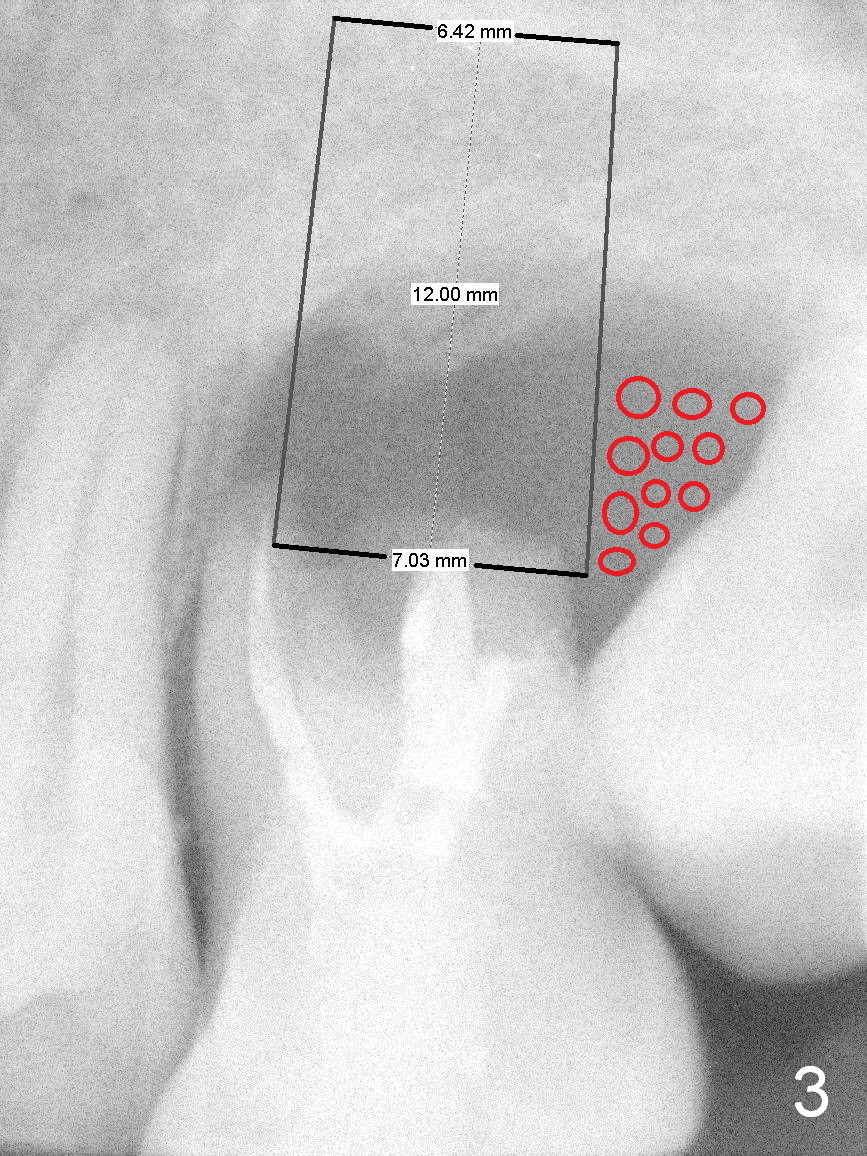

A 42-year-old man (XK) has perio-endo disease at the tooth #14. After root canal therapy (Fig.1), the tooth remains nonsalvageable. The bone loss is extensive (Fig.1 *) and uneven (more bone mesially than distally) after extraction (2% Xylocaine/1:50,000 Epinephrine). A bone-level implant is placed in an ideal depth (Fig.3 UF; Fig.4 SM), irrelevant of the gingival margin, first. Place bone graft distally (Fig.3 red circles) before choosing a proper abutment. For example, there is plenty of combination to choose cuff and abutment lengths for a SM or UF implant (Fig.4).